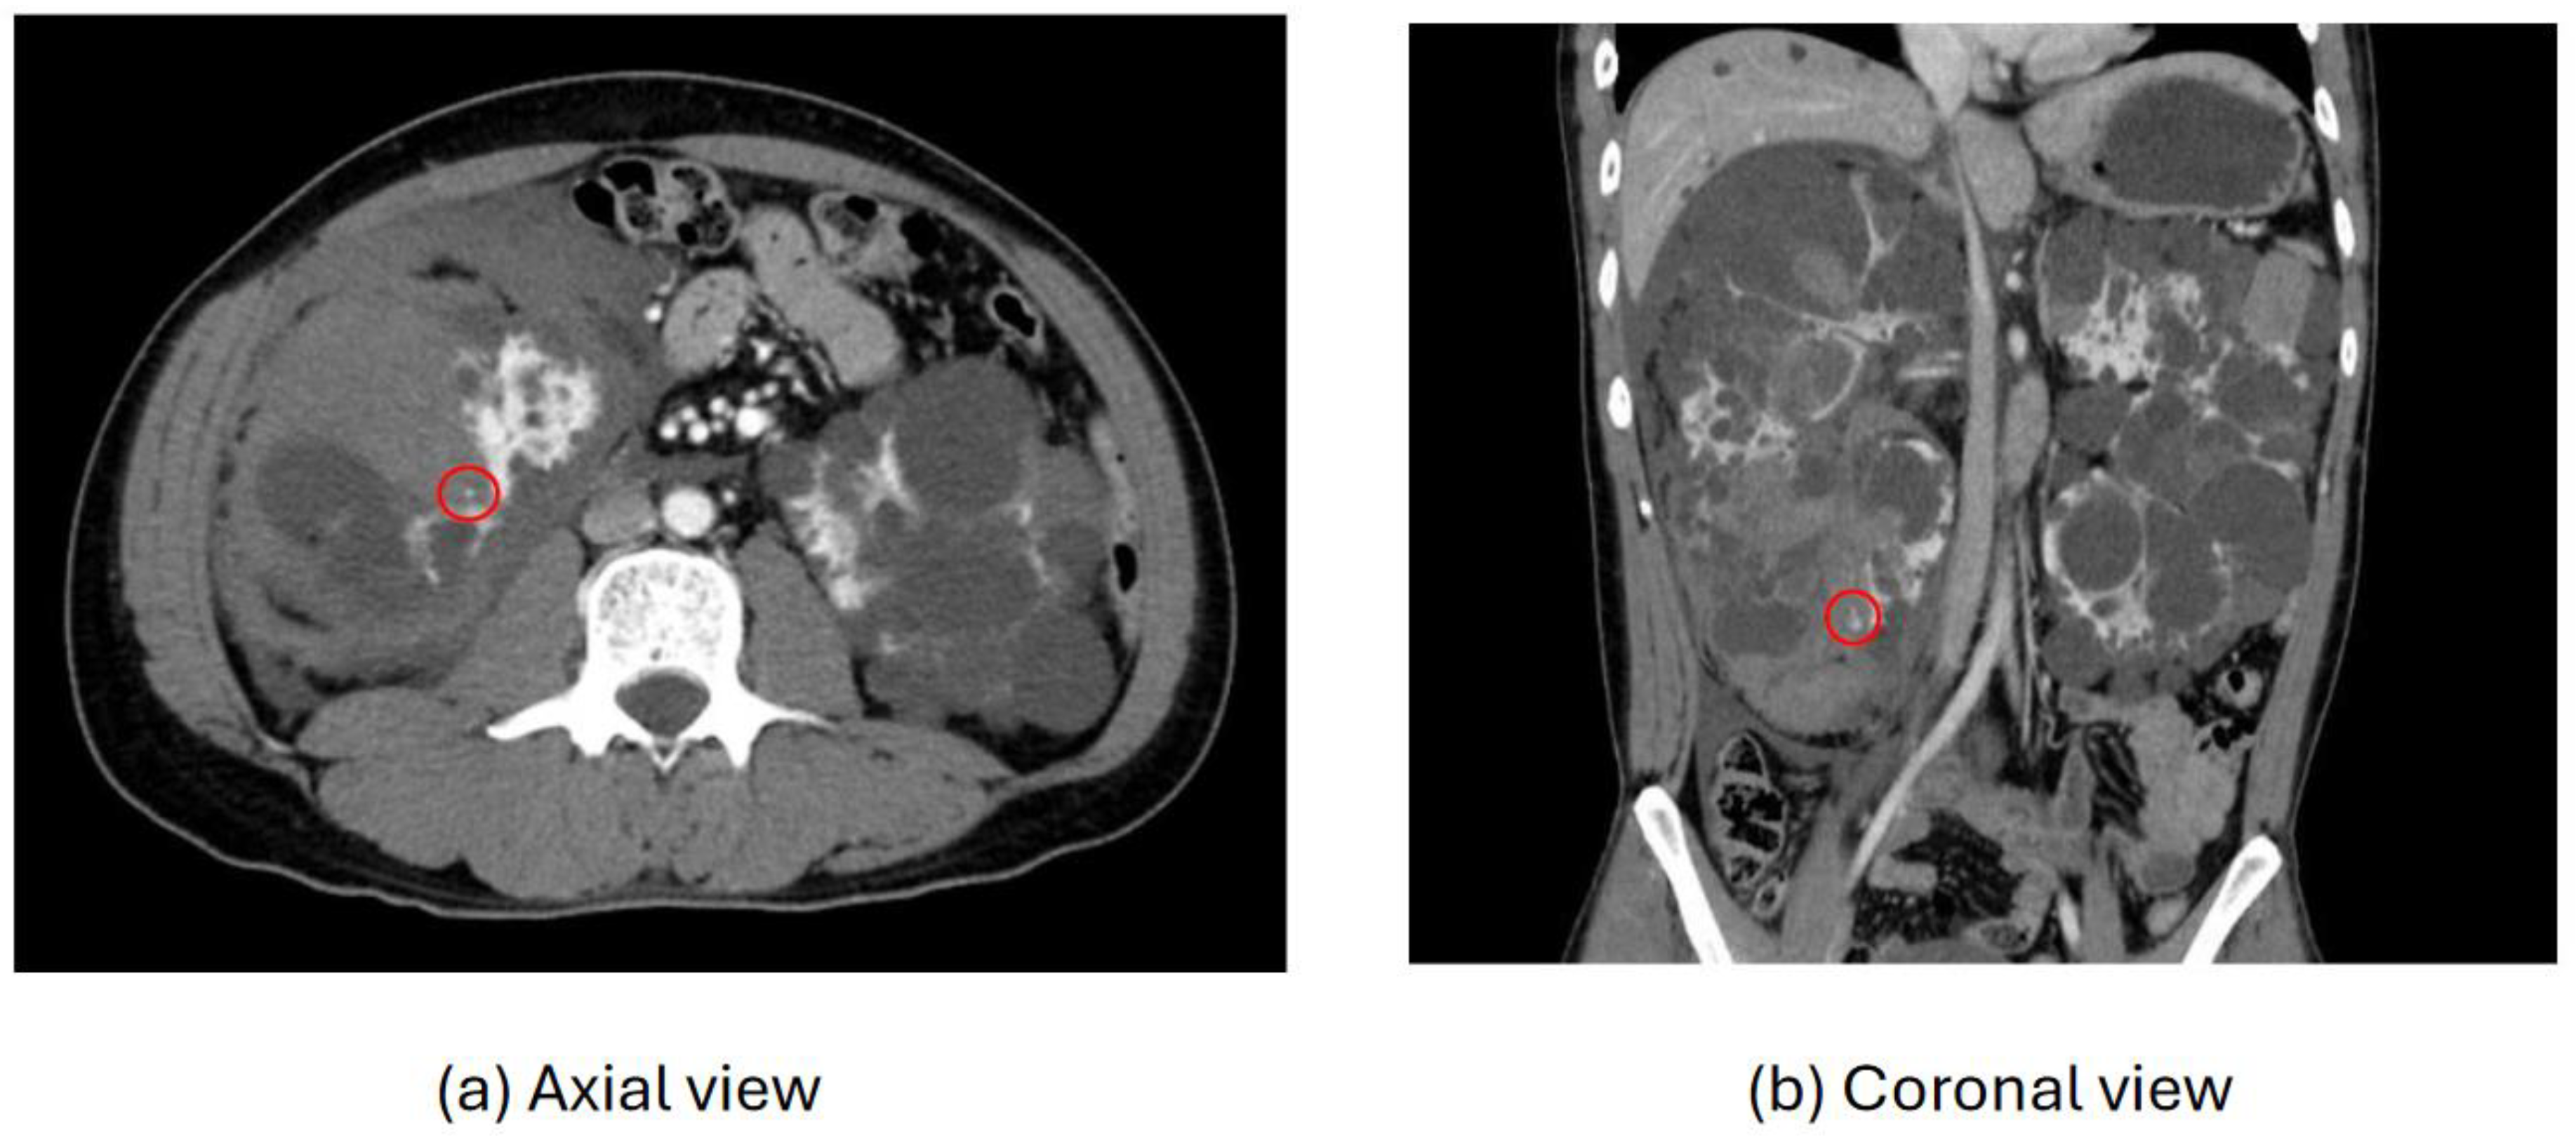

As an illustration, Figure 4 depicts extravasation from kidney angiomyolipoma, a condition characterized by the formation of benign tumors in the kidney. Patients with this condition may experience a range of symptoms, including anemia, fever, pain, or high blood pressure. In cases where tumors grow, treatment such as embolization or surgery may be necessary to mitigate the risk of bleeding.

Figure 5 illustrates extravasation resulting from the rupture of hepatocellular carcinoma in a 68-year-old male patient. This individual had previously undergone transcatheter arterial chemoembolization, a minimally invasive and targeted treatment utilized for managing certain advanced liver tumors that are not amenable to surgical removal. Following the rupture, the patient was admitted to the hospital in a state of hypotension, characterized by low blood pressure. This case underscores the importance of closely monitoring patients with hepatocellular carcinoma, particularly those who have undergone chemoembolization, for potential complications such as extravasation.